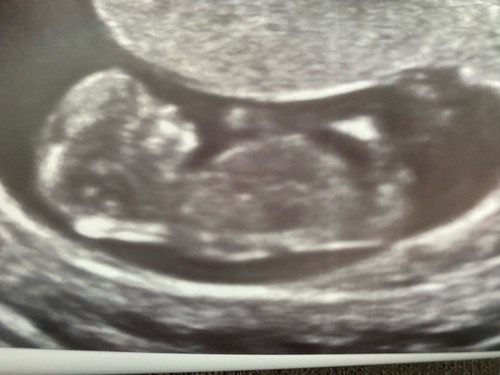

Hier heb ik nog een paar foto’s erbij maar denk dat die ene die ik eerder al stuurde het meest duidelijk is. Ik ben benieuwd wat jullie denken!

Hier heb ik nog een paar foto’s erbij maar denk dat die ene die ik eerder a ...

💗